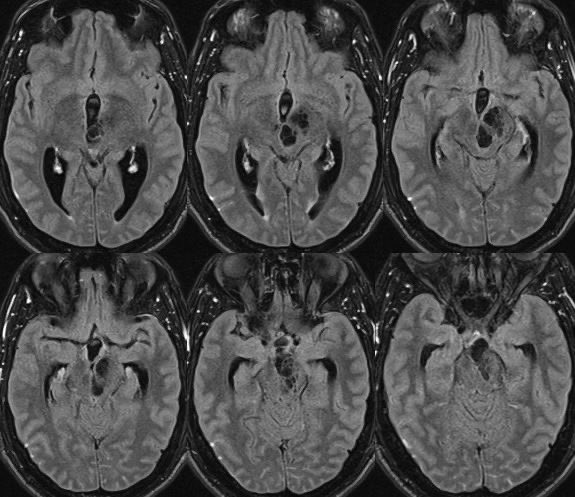

What is the most likely diagnosis in this 30 y/o M presenting with headaches? 🧠

🔷More images in 🧵